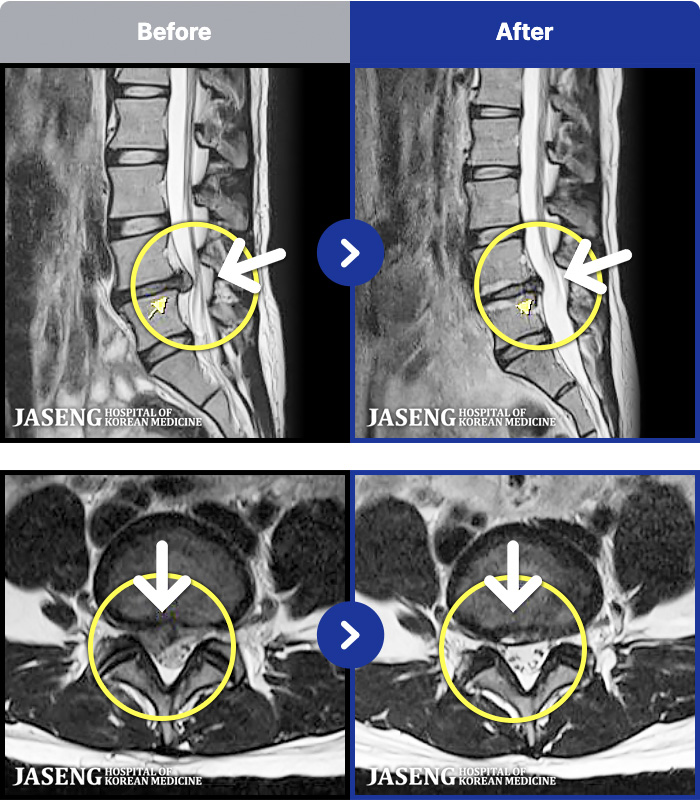

94 MRI ũ ʸ Ȯϼ.

ȯںп Ǹ ǿ ԿǾ, ο ġ ۿ Ƿ ġḦ Ͻñ ٶϴ.